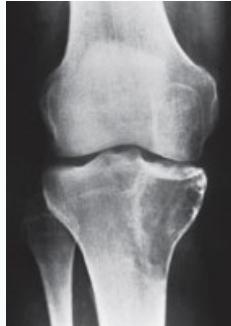

Giant-Cell Tumor

- Unknown origin:

- Giant cells abundant

- Behavior:

- One third benign

- One third locally aggressive

- One third (less) with distant metastasis

- Young adults

- Common sites:

- Around knee

- Proximal humerus

- Distal radius

Radiological Features

- Eccentric lesion:

- Radiolucent

- Soap bubble

- Abuts (adjacent) against the joint

- Thin cortex

- Margins may be clear / unclear:

- Depends on aggressiveness

- Treatment:

- Curettage & bone grafting

- More wide excision in recurrent and aggressive lesions

Source: Bone Tumors A Practical Guide to Imaging